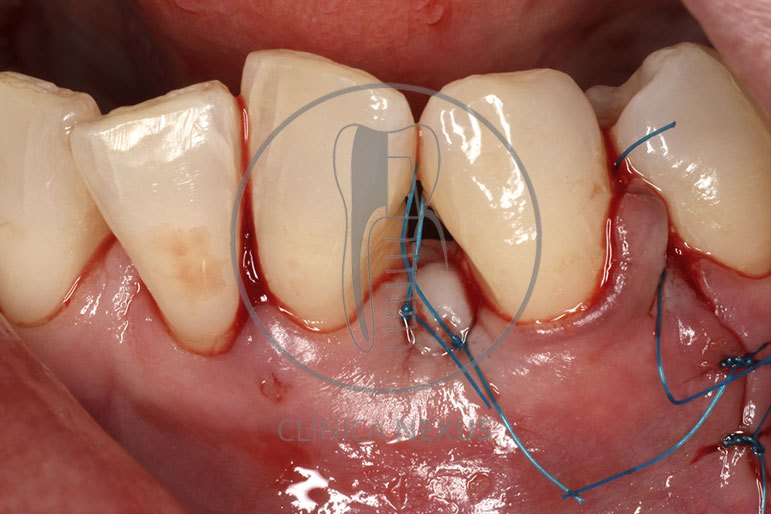

Tratamiento de defectos periodontales infraóseos en sector antero-inferior empleando gel de amelogeninas (Emdogain®) en combinación con un aloinjerto óseo (Biobank®). Paciente de 64 años, sin problemas médicos de relevancia, que presenta una periodontitis leve generalizada, pero asociada a presencia de defectos óseos verticales profundos a nivel de los espacios interdentales entre los caninos y los incisivos laterales inferiores. Tras la pertinente fase higiénica, se llevó a cabo una cirugía periodontal regenerativa, en la que, tras eliminar el cálculo subgingival (factor causal), se empleó una combinación de amelogeninas con un aloinjerto, para promover la regeneración tisular del periodonto perdido. Las imágenes clínicas y radiológicas, al año de seguimiento, reflejan un resultado terapéutico óptimo, con regeneración completa del tejido periodontal y mejora del pronóstico de los dientes involucrados.